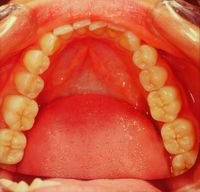

File:Clicker end2 .jpg|'''Figure 9b:''' Occlusal view of functional neuro-evoked rehabilitation and incisal normocclusal restoration with two crowns in Empress (work performed in 1992)

The finalization of the definitively diagnosed clinical case of DTMs resulted in a restoration of the masticatory function, disappearance of the symptoms as well as an aesthetic improvement. The various phases of the rehabilitation can be followed in the gallery of images in figure 9. In particular, the Functional Neuro-Evoked Centric position is not only centered having moved slightly to the right but also retruded. It is interesting to make a comparison with figure 5a to understand the spatial differences. Element 22, in fact, is no longer in crossbite but in a head-to-head position while element 23 has a much more incisal centric contact with respect to the previous clinical situation, so as to note the occlusal space in the medial area of element 24 which it was generated with the current mandibular spatial position determined with the Functional Neuro Evoked Centric. This new occlusal arrangement was only possible because the stable and mainly frozen centric position in the molar sector. The molars through the previously exposed neuromotor balance on the centric cusp stabilize the occlusion and generate a bilateral balance in the mandibular movements as will be shortly described.